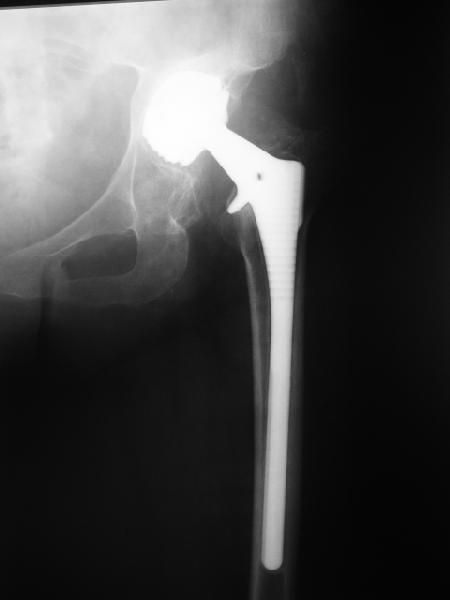

Август 2002 г.

24 апреля 2005 г. правый сустав фас (тут и болит)